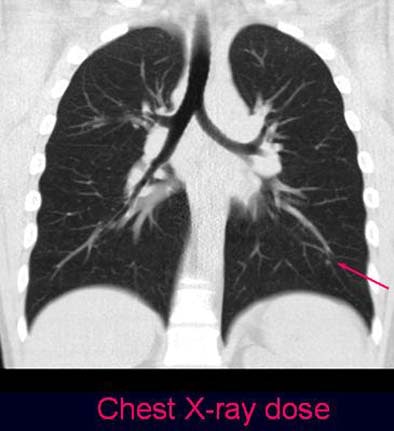

![]() |

| Coronal view of ultra-low-dose protocol reveals a solitary nodule in a 36-year-old patient with monolateral breast cancer (no histologic assessment was available). |